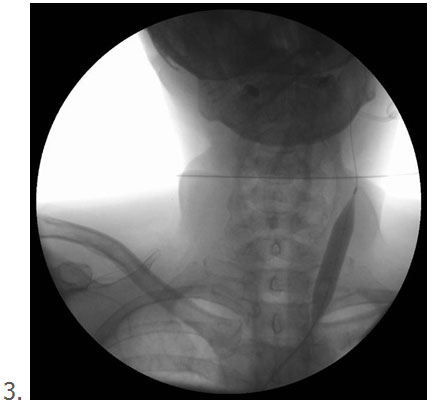

3 4

1. Contrast ingespoten in de ader loopt weg via collateralen, beperkte vernauwing maar vermoedelijk opent het klepsysteem niet volledig

2. Ballon met een deuk ter hoogte van de vernauwing

In de praktijk zie je bij het opblazen van een goed gekozen ballon, dat de ballon voor en achter het letsel eerst gaat opblazen. Goed gekozen bedoel ik de juiste diameter van ballon ten opzichte van de ader. Er blijft midden in de ballon op de plaats van de vernauwing een deuk in de ballon bestaan. Dan voert men de druk in ballon op tot deze deuk verdwenen is (meestal 12-14 atmosfeer en soms hoger). Daarna kijk je op de drukmeter waarmee je de ballon opgeblazen hebt, dan zie je meestal nog wat drukverval ontstaan omdat er toch nog een paar vezeltjes meegeven. Dan geef je opnieuw wat druk bij tot aan de druk waarop de ballon volledig is gaan open staan. En zo volg je dit voor 1-2 minuten totdat er een stabiele situatie is zonder drukverval.